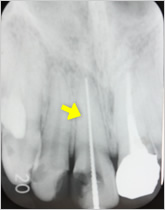

感染根管処置症例.1

主訴:2日前にかけたが、痛みやしみる症状はない。

- 被せ物を外し、過去に行った根管充填が不十分だった為、再度感染根管処置を行う。

- 1番細いファイルを使って、未治療の根の先まで到達したことを確認。

- ファイルを使って根っこの長さを測定・根管形成(根管-神経が入っていた管-を根管充填しやすい形に整えること)

- 根管充填剤が根尖(根っこの先端)まできっちりと充填されている。